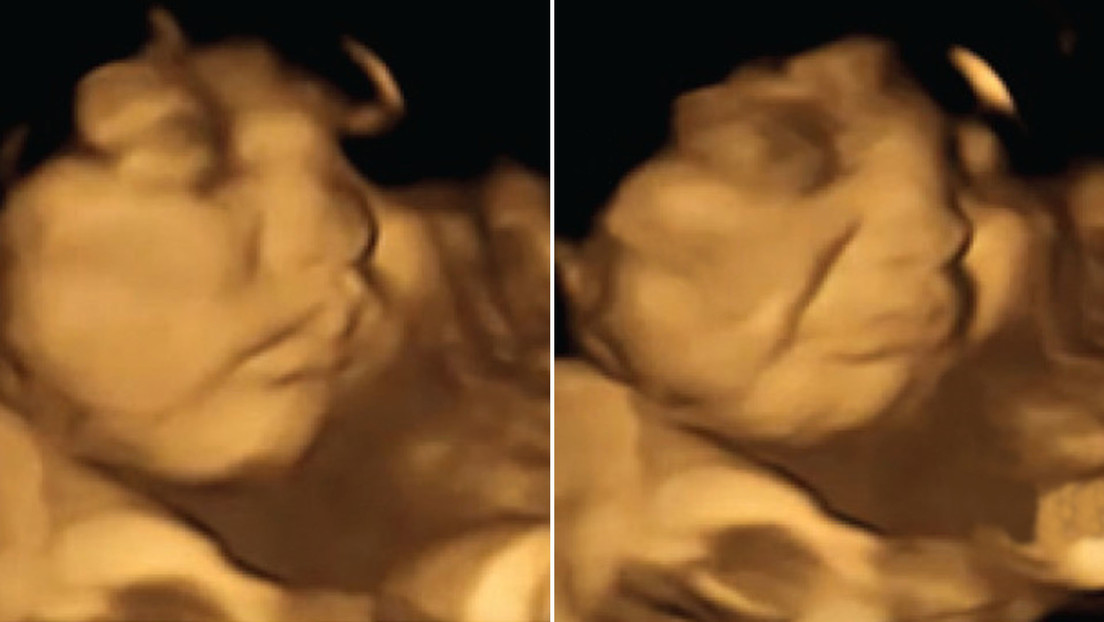

Muestran por primera vez cómo los bebés reaccionan a olores y sabores mientras están en el útero

"Fue realmente sorprendente ver la reacción de los bebés nonatos a los sabores de col rizada o zanahoria durante los escaneos